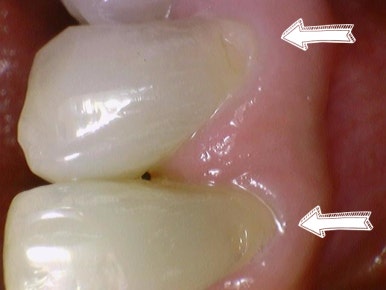

치경부마모증 사진

치경부 마모

치아 목 부위의 치아 겉부분이 패여 있는 것을 볼 수 있습니다. 이런 치경부 마모로 인해 시린증상이 흔합니다. 치아 속에는 치아마다 치아신경이 있는데 이 치아 중간에 있는 치아신경이 치아로 덮혀있어야 하는데 치아가 패이면서 바깥환경과 가까워지니 많이 시리게 됩니다.

환자분들이 "잇몸이 패였어요"하고 찾아오는 경우가 많으신데 잇몸이 패였다기 보다는 치아가 v자 모양으로 패인 것이라고 생각하면 되겠습니다. 이런경우에 잇몸패임 은 잘못된 표현이라고 볼 수 있겠습니다.